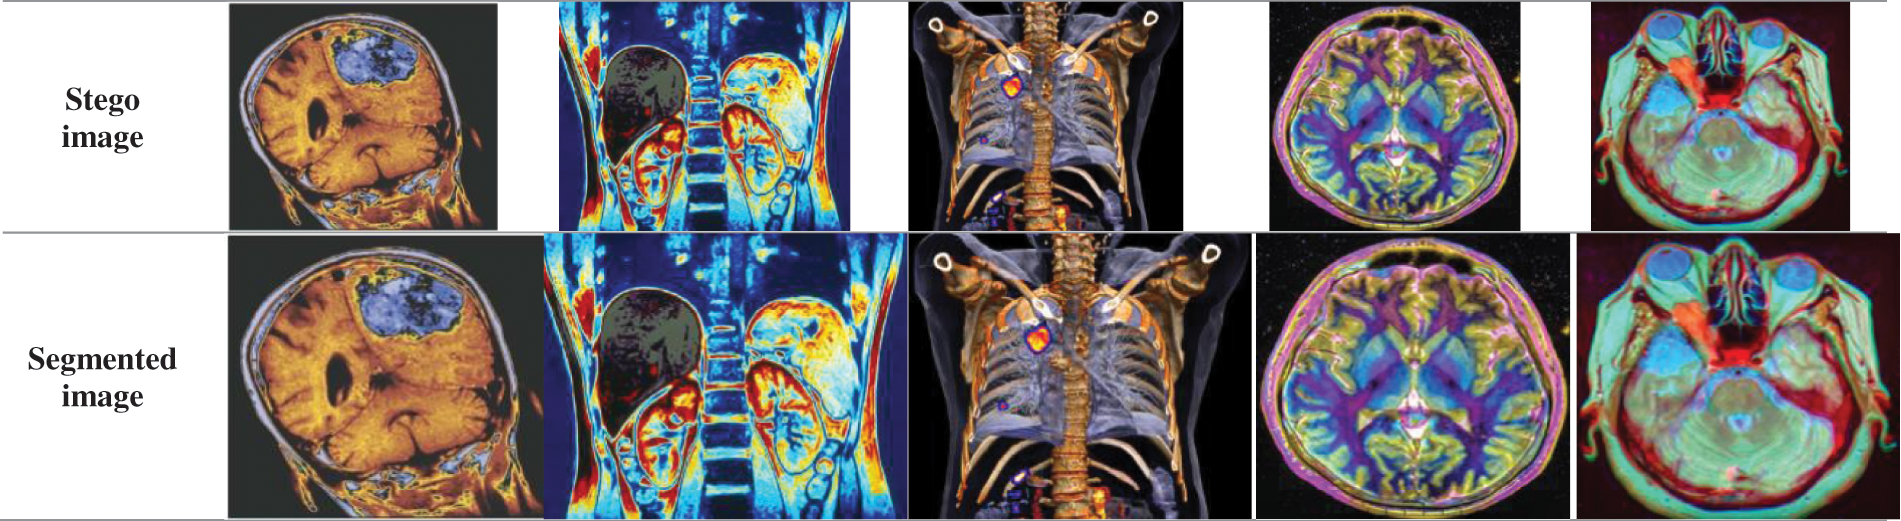

Similar to the method of LSB-based image steganography that involves hiding the secret report into the secret image, the encrypted secret image containing the secret report is hidden inside the cover image using the same technique. The binary representation of the pixel values of the encrypted image with the secret report in it is hidden first in the red component, followed by the blue and the green components of the cover image, as shown in Fig. 9. Next, we segment the cover image with the ciphered secret medical image and the secret report embedded in it into multiple parts (16 to be specific), as shown in Fig. 10. Each part is then separately sent to the receiver. This segmentation makes it very difficult to obtain the total image, and it makes obtaining the information inside the image difficult.

Figure 9: Resulting stego images

Figure 10: Segmented image for each cover image